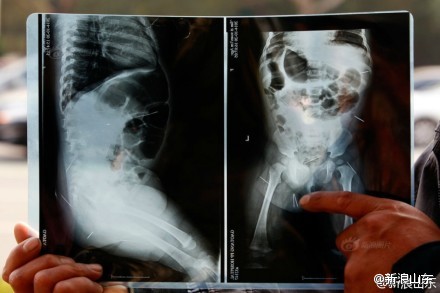

這兩天,聊城11月女嬰被扎12根針牽動著網友的心。父母發現11個月大的小子萱屁股上有小紅點,還總是哭。送到醫院拍片子發現12根鋼針插滿了小子萱的臀部、腹腔、盆骨等部位。

誰都沒有想到聊城11月女嬰被扎12根針,因為鋼針深入體內,從外表根本看不出來,醫生表示取針的難度非常大。

小子萱所在的村子,村民們捐款3000多元,網友的捐款也超過了2萬元。在北京兒童醫院新拍攝的CT顯示:5根鋼針靠近內臟,可能有危險,將留院觀察。

23日上午,專家提出了初步治療方案,因為孩子太小,不能一次性把針取出來,只能先取出腹部最危險的3根針,而取一根針至少要花兩個小時。